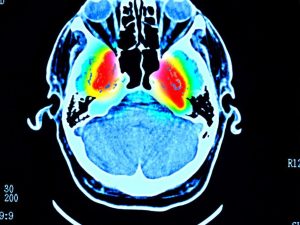

وفي تسعينيات القرن الماضي، اكتشف فريق فرنسي من جرونوبل وسط شرق البلاد، أن التحفيز العميق لمنطقة من الدماغ، وهي النواة تحت المهاد، له تأثير علاجي كبير ضد أعراض هذا المرض.

وتقوم التقنية على زرع قطبين كهربائيين في الدماغ، لتحفيز النوى تحت المهاد بتيار كهربائي ضعيف.

القطبان الكهربائيان اللذان يتم توصيلها بصندوق يحتوي على بطارية مزروعة تحت الجلد، يرسلان نبضات تعيد الأداء الطبيعي للشبكات العصبية التي تعتمد على الدوبامين، الذي يتحكم في المهارات الحركية على وجه الخصوص.